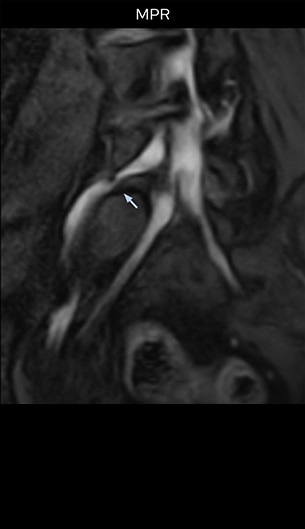

“Although symptoms of typical disc herniation and atypical hernia are very similar, the actual site of herniation is different. It is therefore important to characterize the nerve’s condition both inside and outside of the intervertebral foramina. “Conversely, if we see no abnormality in NerveVIEW, we can assume at least that there is no severe condition that requires surgery. Like this, it can help us avoid unnecessary surgery. NerveVIEW can have a tremendous impact in this way.”

“NerveVIEW is really useful for those cases where a nerve disorder is strongly suspected based on the clinical examination but our regular MRI images do not show any findings. These atypical herniations and spinal canal stenosis, occurring in 5% to 15% of the total lumbar herniation/stenosis cases are our main target when using NerveVIEW,” says Dr. Yabuki.

“The intra-luminal signal of veins, especially around the intervertebral space, can be suppressed well with NerveVIEW. As a result, we can easily observe the detailed nerve structure around the posterior ganglion,” he says. “This is why we use 3D NerveVIEW for intraforaminal stenosis and extraforaminal stenosis/herniation (lateral disc herniation). On the other hand, if herniation is suspected to exist inside the dorsal root ganglion (DRG), balanced TFE or ProSet-FFE is applied. NerveVIEW is not suitable for evaluating the median type of herniation.” The SE-EPI DWI-based method for MR neurography works well for large FOV exams like whole-body MRI, but focal examination of nerves is often limited by the attainable spatial resolution (both inplane and slice direction) and geometric distortion. “3D NerveVIEW achieves higher in-plane resolution – close to our other routine spine sequences – and the source images can be used instead of adding a fat-suppressed T2-weighted sequence,” Tanji says.

“Recently, the two surgical methods extreme and oblique lateral interbody fusion (XLIF and OLIF) have become mainstream for minimally invasive treatment of lumbar spinal canal stenosis and intervertebral foramen stenosis. With these surgical techniques, the spine is approached from the flank, and prior knowledge of the exact anatomy of the lumbosacral plexus would be extremely helpful. To that end, high slice resolution (less than 1 mm acquisition) that enables sharper sagittal MPR images will be needed.”